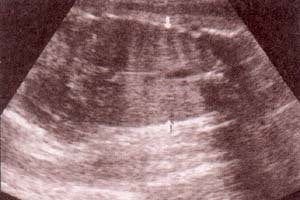

fig 28. – (a). pulmones corte coronal. 32 semanas. |

fig. 28. – (b). corte transversal. 32 semanas. |